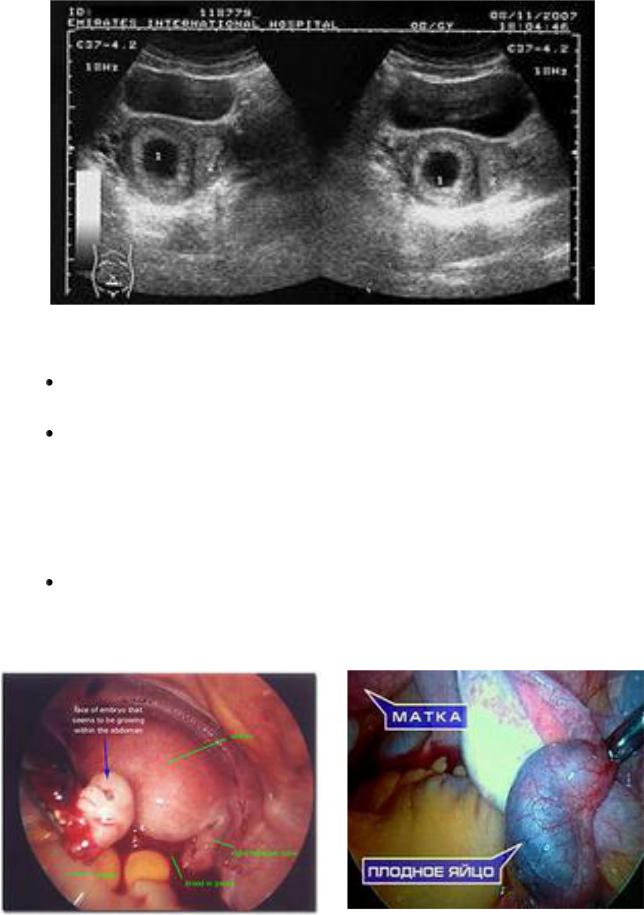

УЗИ: отсутствие плодного яйца в полости матки, многослойный эндометрий, свободная жидкость в дугласовом пространстве и в брюшной полости, возможно обнаружение эктопически расположенного плодного яйца (рис.1, 2).

Рис.1. УЗИ-картина внематочной беременности.

12

Рис.2. Эхо-картина внематочной беременности.

Лапароскопия: кровь в брюшной полости, синюшно-красная утолщенная маточная труба, гематосальпингс, перитубарная гематома, возможно, разрыв трубы (рис.3, 4).

Рис. 3, 4. Лапароскопическая картина трубной беременности.